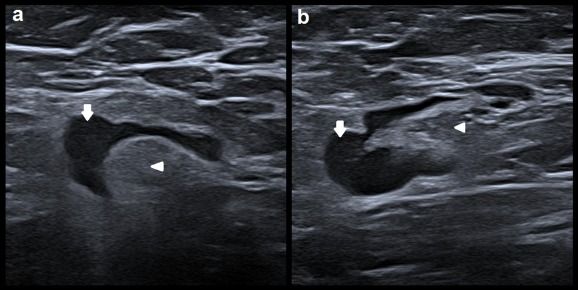

When it comes to differentiating between malignant lymph node changes and benign lymph node changes due to COVID-19 vaccination, combining a machine learning model with ultrasound may be more beneficial than visual ultrasound assessment by radiologists.

The retrospective study, recently published in the European Journal of Radiology, examined a machine learning model with ultrasound images drawn from patients who had routine breast and axillary lymph node assessment between November 2018 and February 2020 at a hospital in Barcelona. The study authors noted that the ultrasound images, acquired by breast imaging radiologists, came from patients with breast cancer as well as patients without breast cancer.

After training of the deep learning model with 10 cases and 61 controls, the study authors compared the effectiveness of the model to visual lymph node assessment by radiologists with a review of 109 ultrasound images from 36 cases and 73 controls. Visual inspection of axillary lymph nodes via ultrasound by radiologists resulted in 69.7 percent accuracy, 41.7 percent sensitivity and 83.6 percent specificity, according to the study. In contrast, the study authors noted that use of the deep learning model in concert with ultrasound led to a 92.7 percent accuracy rate, 77.8 percent sensitivity and 100 percent specificity.

“This direct comparison on the same images clearly suggests that the proposed methods can improve radiologists’ performance and also indicate that visual techniques are not enough to correctly classify nodes in patients after COVID-19 vaccination,” maintained Xavier P. Burgos-Artizzu, BEng, MSc, PhD, who is affiliated with the Barcelona Center for Maternal-Fetal and Neonatal Medicine at the Hospital Clinic de Barcelona in Spain, and colleagues.

The study authors noted that software incorporating the deep learning algorithm could prevent unnecessary biopsies and augment decision-making for patients with suspicious lymph nodes revealed during ultrasound exams.